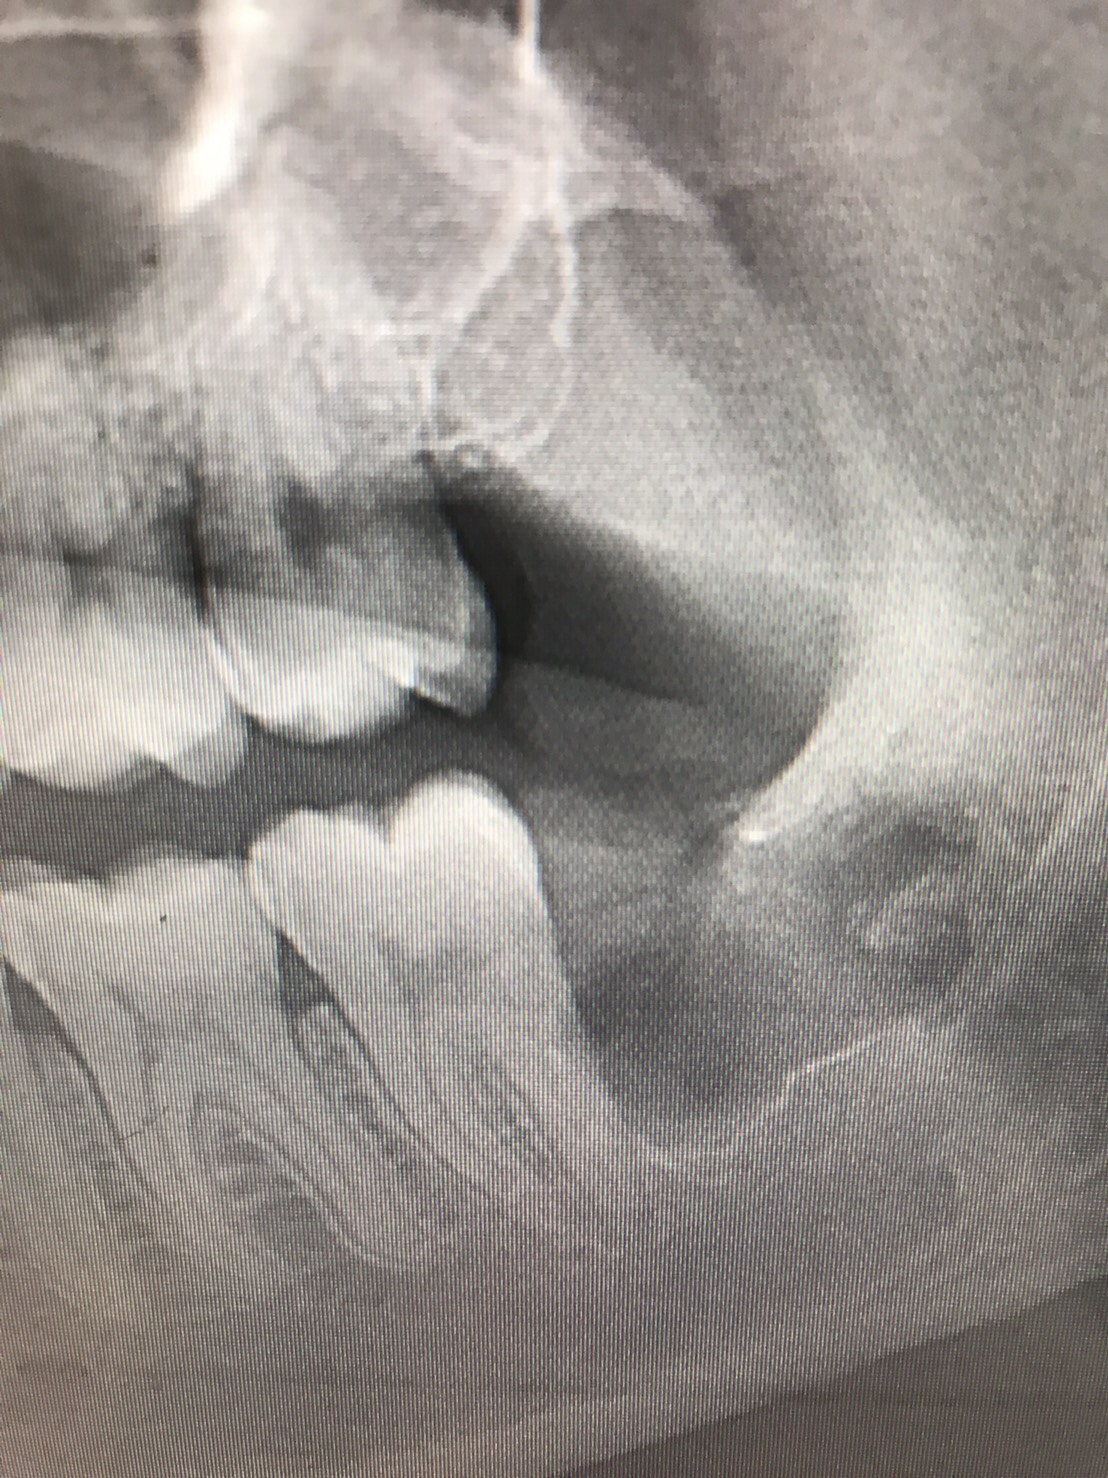

インプラント ソケットリフト法のBefore/After

【Before】

上顎洞(鼻の空洞)までの間隔が4mmしか無いため、しっかりとしたインプラント治療が行えない状態です。

【After】

お鼻の空洞を上げて骨を造成し、十分なスペースを確保することで、しっかりとしたインプラント治療が出来ています。

当院のソケットリフトは最小限の侵襲で骨を造成するので、お顔が腫れたり痛みが出ることがほとんどありません。